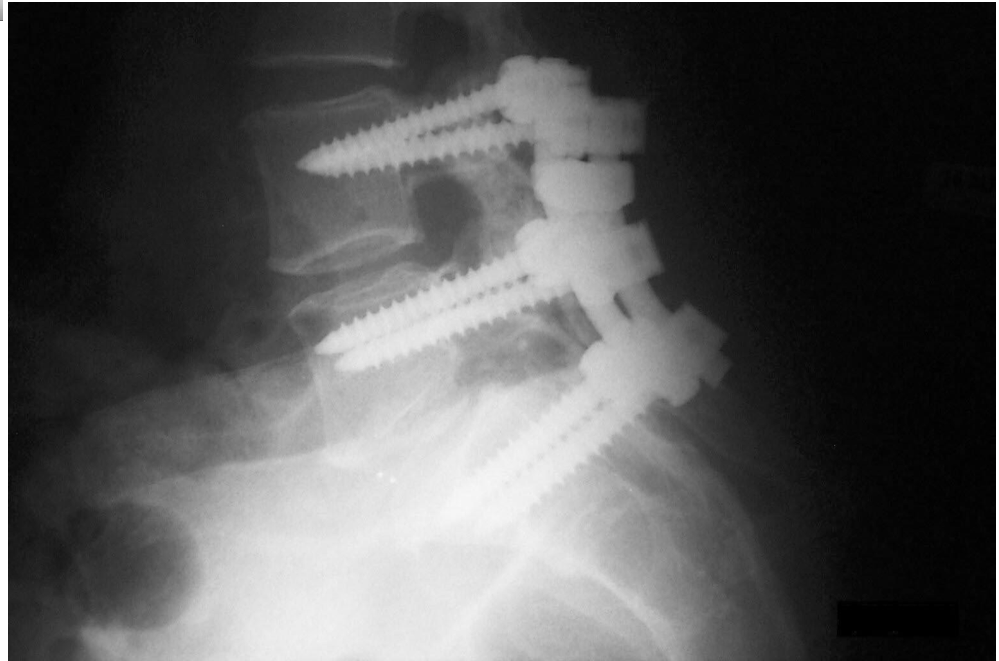

IRM de J.P.PETIT, juillet 2009. P : protrusions discales avec compression de la moelle épinière. G : Glissement de vertèbre

Dans cette arthrodèse on fait du même coup disparaître deux articulations discales. Du coup, c'est la suivante, au dessus, qui déguste. Si les corps vertébraux sont décalcifiés ( avec l'âge ) les vis se barrent, et comme dans cette région lombaire la moelle épinière explose en une multitude de nerfs formant " la queue de cheval " les chance de loger une vis au contact d'un nerf sont non négligeables. J'ai croisé maints ratages de ce genre : des hommes-épaves.

Je n'ai jamais craint de passer sur une table d'opération. Il y a deux ans c'était pour une hernie sus-ombilicale. Dix ans plus tôt un " canal carpien double " ( voir ma BD le Spondyloscope ). La chirurgie rend bien des service. Mais là, ça vous tente ?